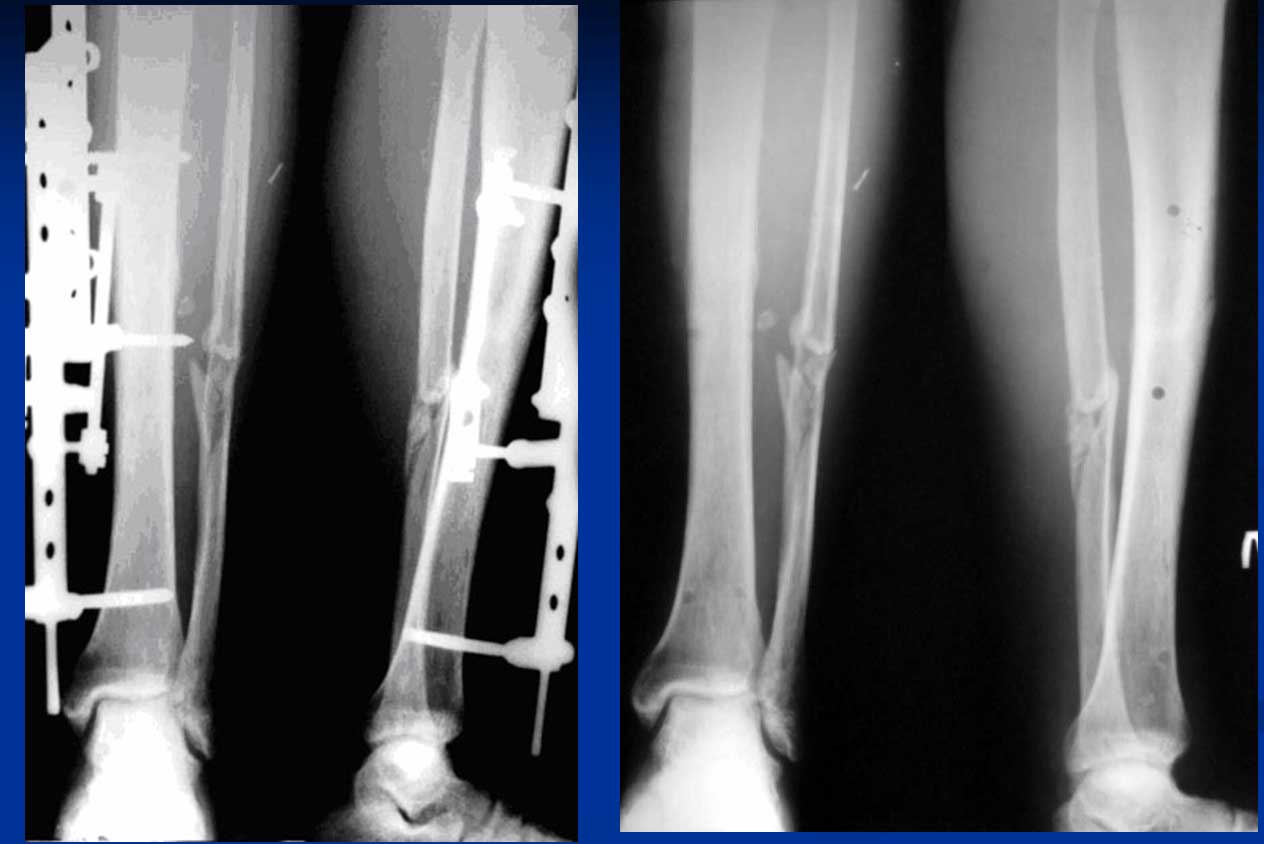

По мере формирования сращения прочность соединения отломков постепенно увеличивается. На этом этапе целесообразна постепенная дестабилизация аппарата, чтобы область формирующегося сращения подвергалась возрастающим функциональным нагрузкам. Это достигается удалением спиц и демонтажом кольцевых опор с переводом аппарата в монолатеральный, что также обеспечивает и больший комфорт для пациента (рис. 5).

рис. 5. Вид аппарата после снятия внешнего компрессирующего модуля

Клинический пример, демонстрирующий описанную технологию, представлен на рентгенограммах (рис. 7). Пациент 30 лет получил поперечный перелом костей голени в средней трети диафиза во время спортивных соревнований в результате удара ногой по голени. При поступлении выполнен остеосинтез спице-стержневым аппаратом. Через 2 месяца демонтирован спицевой модуль, еще через месяц снят монолатеральный аппарат. Общий срок пребывания в аппарате составил 3 месяца.

рис. 7. Рентгенограммы пациента с косопоперечным диафизарным переломом костей голени, которому был выполнен остеосинтез спице-стержневым аппаратом (а - до лечения, б - после остеосинтеза, аппарат включает спицевой модуль, в - перед снятием аппарата в срок три месяца, спицевой модуль демонтирован месяц назад; г - результат в четыре месяца).